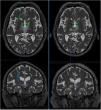

La imagen del tensor de difusión o tractografía es una técnica no invasiva que permite visualizar vías de sustancia blanca en el cerebro mediante la identificación de la principal dirección de las fibras en cada vóxel de la imagen del tensor de difusión de la RM58. Yamada et al. delimitaron el tracto cerebelorrubrotalámico con esta técnica, seleccionando regiones de interés (ROI) en el núcleo rojo y la corteza motora primaria ipsilaterales y considerando el Vim como el punto de intersección entre dicho haz y el tálamo en la línea intercomisural59. Otros autores han localizado dianas para ECP con tractografía probabilística parcelando el tálamo, con base en estudios de conectividad, predefiniendo regiones del córtex que proyectan sobre el tálamo60 (fig. 3).

Efecto de la talamotomía por ultrasonidos (MRgFUS) sobre el haz dentato-rubro-talámico (DRT). Imágenes de la tractografía del haz DRT procedentes de secuencias DTI en resonancia magnética de alto campo (Skyra,3T,Siemens) pre-tratamiento (izquierda) y post-tratamiento (derecha). El haz DRT se observa en el tálamo a nivel del plano intercomisural. En los cortes axiales y coronales se aprecia la práctica desaparición del haz en las secuencias post-tratamiento, persistiendo el haz contralateral. La cruz indica la localización de la lesión. Imágenes extraídas de software de planificación Iplannet de Brainlab.

Además, se ha publicado un estudio que correlaciona tractografía con talamotomía por ultrasonidos guiados por RM (MRgFUS) y refiere que la distancia final entre la localización de la lesión por ultrasonidos y la diana tomada por imagen directa mostraba una discrepancia de 2,5mm69. Esta variación puede atribuirse a la idiosincrasia del procedimiento, lo que resulta en modificaciones de la energía de los ultrasonidos y, por tanto, en diferente respuesta del parénquima a la lesión (fig. 3).